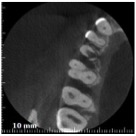

Allora per capirci qualcosa in più ho fatto una cone beam.

Riassorbimento esterno - Cone beam sagittale Riassorbimento esterno - Cone beam frontale Riassorbimento esterno - Cone beam transassiale